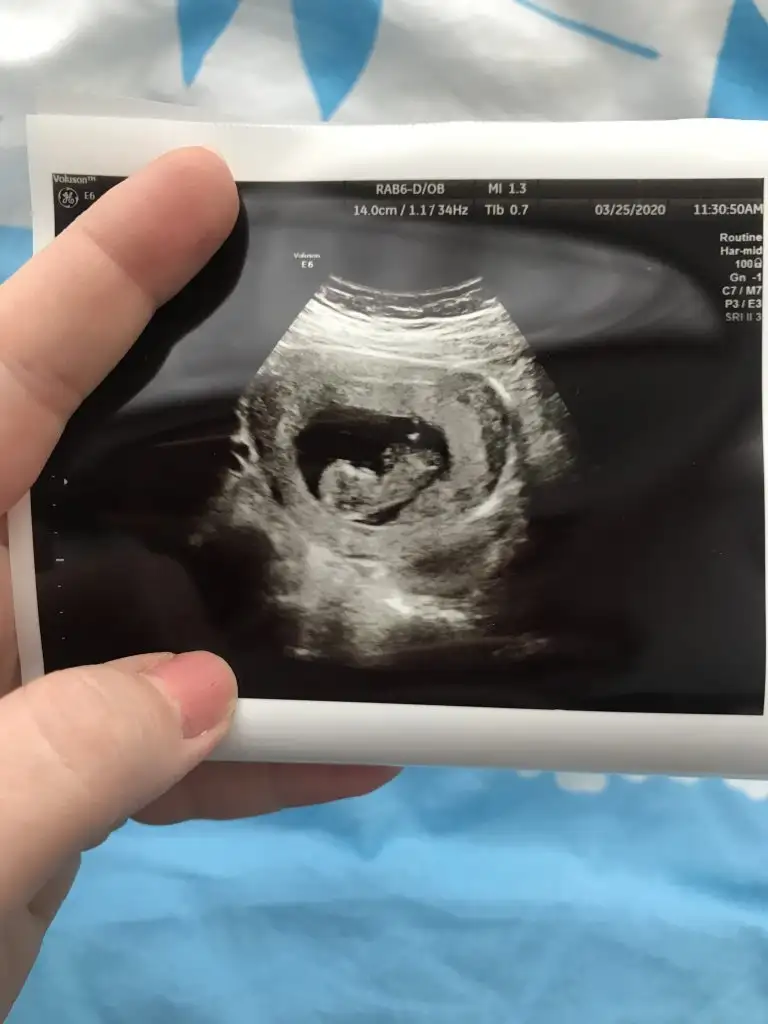

Her iki doktor farkli soyledi cinsiyetini 10ngun sonra kesin soyleriz dedi son fotograflar yeni bacak arasi net dikattli bakinca belki fikrin netlesir belki canimSanki erkek gibi 12 yada 13 hafta usgde paylaşın![]()

Burada kız gibi zaten 12 13 hafta usg istemiştim burada kaç hafta usgHer iki doktor farkli soyledi cinsiyetini 10ngun sonra kesin soyleriz dedi son fotograflar yeni bacak arasi net dikattli bakinca belki fikrin netlesir belki canim![]()